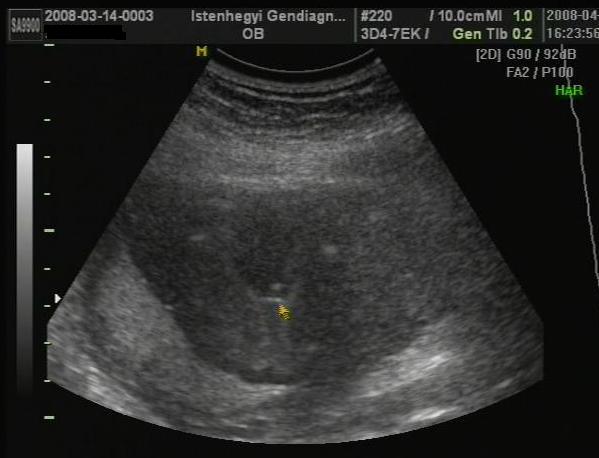

Bogi baba fél feje és lába

Bogi baba fél feje és lába

Bogi feje és keze

Bogi feje és keze